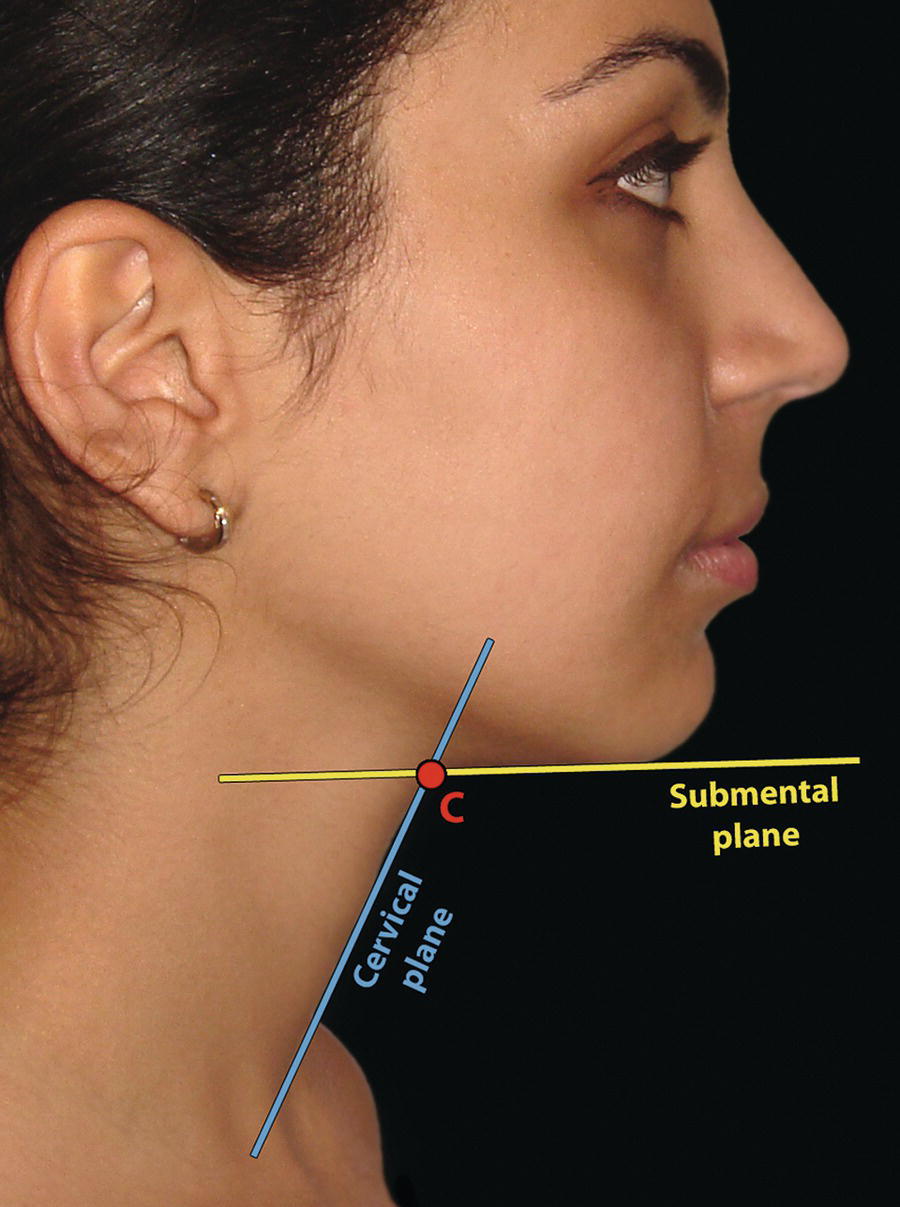

The morphology of the upper aspect of the neck and its transition with the submental region has a major impact on the aesthetics of the lower face. The anterior part of the neck extends no higher than the inferior border of the mandible. The hyoid bone is connected to the mandible by a thin sheet of muscle, the mylohyoids, which form the upper limit of the anterior part of the neck and separate the mouth from the neck. Superficially (i.e. below the mylohyoids) lies the anterior belly of digastric, while lying above it, half hidden under the mandible in the submandibular fossa, is the submandibular salivary gland (Figure 21.1). These structures are covered in by the investing layer of deep cervical fascia, which is attached to the hyoid bone and the inferior border of the mandible. The platysma muscle lies in the subcutaneous tissues. It forms a broad, flat sheet, extending from the deep fascia over the upper part of pectoralis major and the most anterior part of deltoid to the inferior border of the mandible, with some fibres reaching the lateral part of the lower lip. The sternocleidomastoid muscle forms a prominent neck landmark and may be made to stand out by turning the head towards the opposite side against resistance. The two heads of origin are from the sternum and medial one‐third of the clavicle; its attachment is to the mastoid process, which forms a readily visible and palpable bony landmark behind the lobe of the ear (Figure 21.2). Figure 21.1 Submental anatomy in relation to the mandible, with muscle attachments: Despite its importance in facial aesthetics, there is much confusion in terminology relating to the description and analysis of the submental‐cervical region. For example, the cervicomental angle has been described by perhaps half a dozen different methods, depending on the describing authority. Appropriate terminology is essential for the evaluation and accurate description of submental‐cervical aesthetics (Figure 21.3). Figure 21.2 Profile view of the face and neck with superimposed bony and muscular outlines: Cervical point (C‐point or ‘point C’): The innermost (posterior‐superior) point between the submental plane and the anterior aspect of the neck in the midsagittal plane, located at the intersection of lines drawn tangent to the submental region and the anterior neck. Submental plane: A plane or line constructed between the cervical point (C‐point) and the most inferior point on the chin (soft tissue menton, Me’). If C‐point cannot be defined, the submental plane is drawn tangent to the submental contour passing through soft tissue menton. The submental plane is referred to as the ‘throat’ plane by some authorities; the submental length (distance from C‐point to menton) is therefore sometimes referred to as the ‘throat length’. Cervical plane: A plane or line drawn tangent to the anterior soft tissue contour of the neck above and below the thyroid prominence. Figure 21.3 Submental plane, cervical plane and cervical point (C‐point). A thorough understanding of the aetiological factors involved in creating a poor aesthetic contour of the submental‐cervical region is required in order to diagnose and appropriately plan the correction of the aesthetic submental‐cervical angles and contour. The tonicity of the submental‐cervical skin, the muscular support of the neck, the isolated fatty deposits in the submental‐cervical region, the skeletal framework of the mandible and chin, and the spatial position of the hyoid bone are all important parameters in the aesthetic analysis of the submental‐cervical region. An undesirable submental‐cervical contour may result from: It is paramount that the clinical evaluation is undertaken with the patient in natural head position (NHP). Even a small degree of upward or downward tilting of the head must be avoided as it may have a profound effect on the contour of the submental‐cervical region. A number of parameters may be analysed in the clinical evaluation of the submental‐cervical region: Mandibular and/or chin deficiency in the sagittal plane, and/or posterior (downward and backward) rotation of the mandible, often secondary to vertical maxillary excess, may contribute to the undesirable aesthetic appearance of the submental‐cervical region (Figure 21.4). It is helpful to have the ‘Class II skeletal pattern’ patient posture the mandible forward to a more normal sagittal position, which will concurrently stretch the submental soft tissues. If this manoeuvre improves the submental‐cervical aesthetics visually, and tightens the submental soft tissues to palpation, then correction of the underlying skeletal discrepancy is likely to improve the submental‐cervical aesthetics (Figure 21.5). Figure 21.4 Class II jaw relationship due to mandibular deficiency and significant compensatory proclination of the mandibular incisor teeth; the submental‐cervical angle is increased. Figure 21.5 (A) Patient with Class II jaw relationship due to mandibular deficiency. (B) Posturing the mandible forward to a more normal sagittal position will concurrently stretch the submental soft tissues. Figure 21.6 Skin laxity test. The converse is also true. Surgical procedures to set back the mandible, or set down the maxilla causing posterior mandibular rotation, will tend to have undesirable consequences on submental‐cervical aesthetics (see Figure 19.22). The patient must be informed of these potential untoward consequences of orthognathic surgery, and should be advised of the possible future need for aesthetic surgical procedures of the submental‐cervical region. The laxity of the submental‐cervical skin may be evaluated by the skin laxity test: the clinician stands behind the patient and gently pulls the soft tissues upward and backward just inferior and anterior to the ear, simulating a neck lift (Figure 21.6). If the soft tissues are easily displaced upward there is increased laxity of the skin, termed redundant skin.1 If following this manoeuvre there is still submental fullness, the patient has redundant skin and excessive submental‐cervical adiposity. Reduced tonicity of the platysma may contribute significantly to submental fullness.2,3 In addition, the platysma muscle may or may not merge anatomically across the midline. Frequently, excessive submental fullness results not only from redundant skin but from the redundant medial borders of the platysma muscle that fail to meet in the midline. Increased submental‐cervical fat accumulation may be independent of generalized body fat; in some patients subcutaneous fat accumulation in this region may remain despite extensive weight loss. In younger patients the fat usually accumulates between the skin and the platysma muscle. In older patients, the fat may accumulate both deep and superficial to the platysma (Figure 21.9). The quantity of submental fat may be estimated by the submental pinch test: the submental soft tissues are gently gripped between the thumb and index finger.1 This manoeuvre should be performed with the patient both in NHP and with the head extended and contracting the platysma muscle; in this way the clinician may determine whether the submental fat is predominantly supraplatysmal or subplatysmal. Figure 21.7 Platysma view: With the head tilted slightly back in frontal view, grimacing and clenching the teeth will induce contraction of the platysma muscle. The muscular fascicles of the platysma become visible beneath the skin. Figure 21.8 Platysmal bands may be evident in repose in an ageing neck. Figure 21.9 Submental adiposity. Figure 21.10 The definition of the inferior border of the mandible is an important aesthetic parameter as it defines the demarcation between the face and neck. (Detail, Woman’s Head, Leonardo da Vinci, c. 1470–76, Galleria degli Uffizi, Florence.) The definition of the inferior border of the mandible, from the chin to the gonial angle, is an important aesthetic parameter, as it defines the demarcation between the face and neck (Figure 21.10). In frontal view, the transition from the upper aspect of the neck to the inferior border of the mandible has a subtle hourglass appearance, with its superior aspect being well defined by the concavity immediately below the inferior mandibular borders (Figure 21.11).1 The soft tissues of the neck normally closely adhere to the structures underlying them. Lack of definition of the inferior mandibular border may be due to increased soft tissue laxity, fat accumulation, mandibular/chin deficiency or hyoid bone sag. Figure 21.11 In frontal view, the transition from the upper aspect of the neck to the inferior border of the mandible has a subtle hourglass appearance. The submandibular salivary gland envelopes the posterior border of the mylohyoid muscle, half hidden in the submandibular fossa on the medial aspect of the mandible (see Figure 21.1). Submandibular fullness may result from an increase in size of the submandibular gland, laxity of the neck fascial layer or submandibular gland ptosis. Rhytidectomy and platysma plication address this problem indirectly by increasing the fascial support for the gland. However, patients may develop a more noticeable submandibular fullness as the removal of submental fat unmasks the ptotic gland. Partial or complete submandibular gland resection provides definite improvement of submandibular fullness resulting from glandular hypertrophy or ptosis, but may be considered too radical for a patient with a normal‐sized, ptotic submandibular gland. Guyuron et al.4 have described the basket submandibular gland suspension technique, directly supporting the gland onto the inner aspect of the inferior surface of the mandible with a strong piece of fascia. This technique helps eliminate submandibular fullness in patients with normal‐sized, ptotic glands. Resection remains the treatment of choice for the correction of glandular hypertrophy. Figure 21.12 Of the ‘six visual criteria’ of the profile view for ‘success in restoring the youthful neck’, the following are demonstrated: 1 Distinct inferior mandibular border 4 Visible anterior border of sternocleidomastoid muscle 5 Submental‐cervical (submental‐neck) angle between 105° and 120° 6 Sternocleidomastoid‐submental plane (SM‐SM) angle approximately 90°